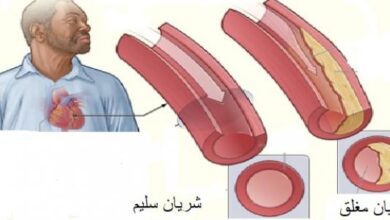

- مرض القلب التاجي (بالإنجليزية: Coronary Artery Disease)[٨]، والذي يحدث نتيجة تراكم الترسبات والمواد الدهنية على جدران الشرايين التاجية، والشرايين التاجية هي المسؤولة عن تزويد القلب بالدم.[٩]